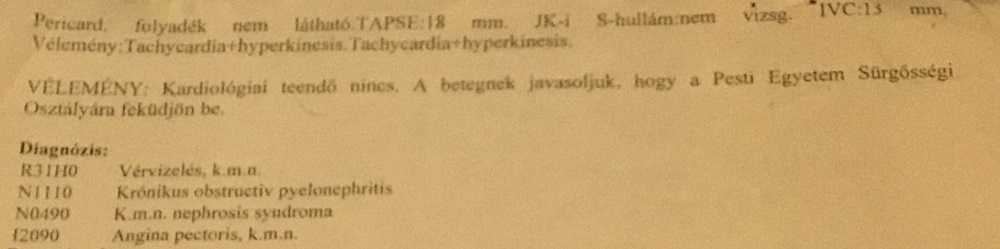

Új háziorvosunk, Dr Jordán Gyula rögtön beutalta kardiológushoz a fiamat. 1 napon belül elérte, amire az ország, főváros I. sz. Belgyógyászati Klinikáján Ledó Nóra azt állította, 5-6 hét – egy ilyen súlyos, akut betegnek. Amikor Dr Gödölle Zoltán meglátta a fiamat kiabálni kezdett: „Hogy néz maga ki? Én ismerem az egészségügyet, de maga nem tudta magát képviselni? Maga 3 hónapig nem kapott antibiotikumot??? Óriási bajban van a szervezete!” Dr Gödölle négy diagnózist írt le: vérvizelés, krónikus obstructiv pyelonephritis, nephrosis szindróma, angina pectoris. Teljesen ki volt borulva, hogy ilyen objektív, ordítóan pozitív leletekkel, hogy nem történt semmi 3 hónapig? És akkor még nem tudta azt, hogy mi két-három naponta próbáltuk elérni, hogy kezelést kapjon a fiam, vagy fővárosi szakklinikán, vagy sürgősségin, vagy megyei kórházban… Ha tudta volna, hogy 31 alkalommal tettük ezt összesen…

Súlyos kétoldali vesefájdalommal érkezett a fiam, aki túlélte a szeptikus állapotot, amivel itt volt először. Erre következetesen bal veséről írtak a felvételkor és a CT leletben. Merthogy történt egy CT Angiográfia. A vesemedencék (pyelonok) extrarenális helyzetűek – írta a távleletező viszonylag kezdő radiológus. A tatabányai kórházban ezt nem beszélték meg szakemberrel. Ami azért lett volna kulcsfontosságú, mert Zsoltnál azok nem veleszületetten voltak ilyenek, ahogy gondolták, hanem a fertőzés ideje alatt keletkeztek, akkor „csúsztak ki helyükről a vesén kívülről, nem is kicsit!” Ugyanezt igazolta az 1 hónappal korábbi MR urográfia is. Gyakorlatilag negatív leletet adtak ki, és a fiamat hazaküldték, miközben a veséi kiszakadtak a fájdalomtól és a neuropátiától (Cipro) úgy égett a teste, hogy az szavakkal nem fejezhető ki, elképesztő erő kellett, hogy kitartson. Mivel a fiamnak az addigra már 10 éve tartó betegsége alatt több tucat CT, CTA, MR, MRA és más képalkotó készült, pontosan visszanézhető milyenek voltak a veséi, milyen anatómiájúak, milyen vesékkel született – és hát nem extrarenális pyelonokkal. Teljesen normális anatómiájú, sosem fájó veséi voltak. Talán úgy mondanák szakmailag, intrarenalis pyelonjai voltak, a vesén belüli helyükön, ahogy kell. A vesén kívülre került vesemedencék a súlyos, közel 4 hónapja tartó kezeletlen vesemedence-gyulladás következményeként „csúsztak ki”. És lehet, hogy feszítik a magukkal „húzott” szöveteket, idegeket és ezért veszik meg a fiam a fájdalomtól!